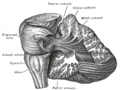

صور اضافية

Dissection showing the course of the cerebrospinal fibers